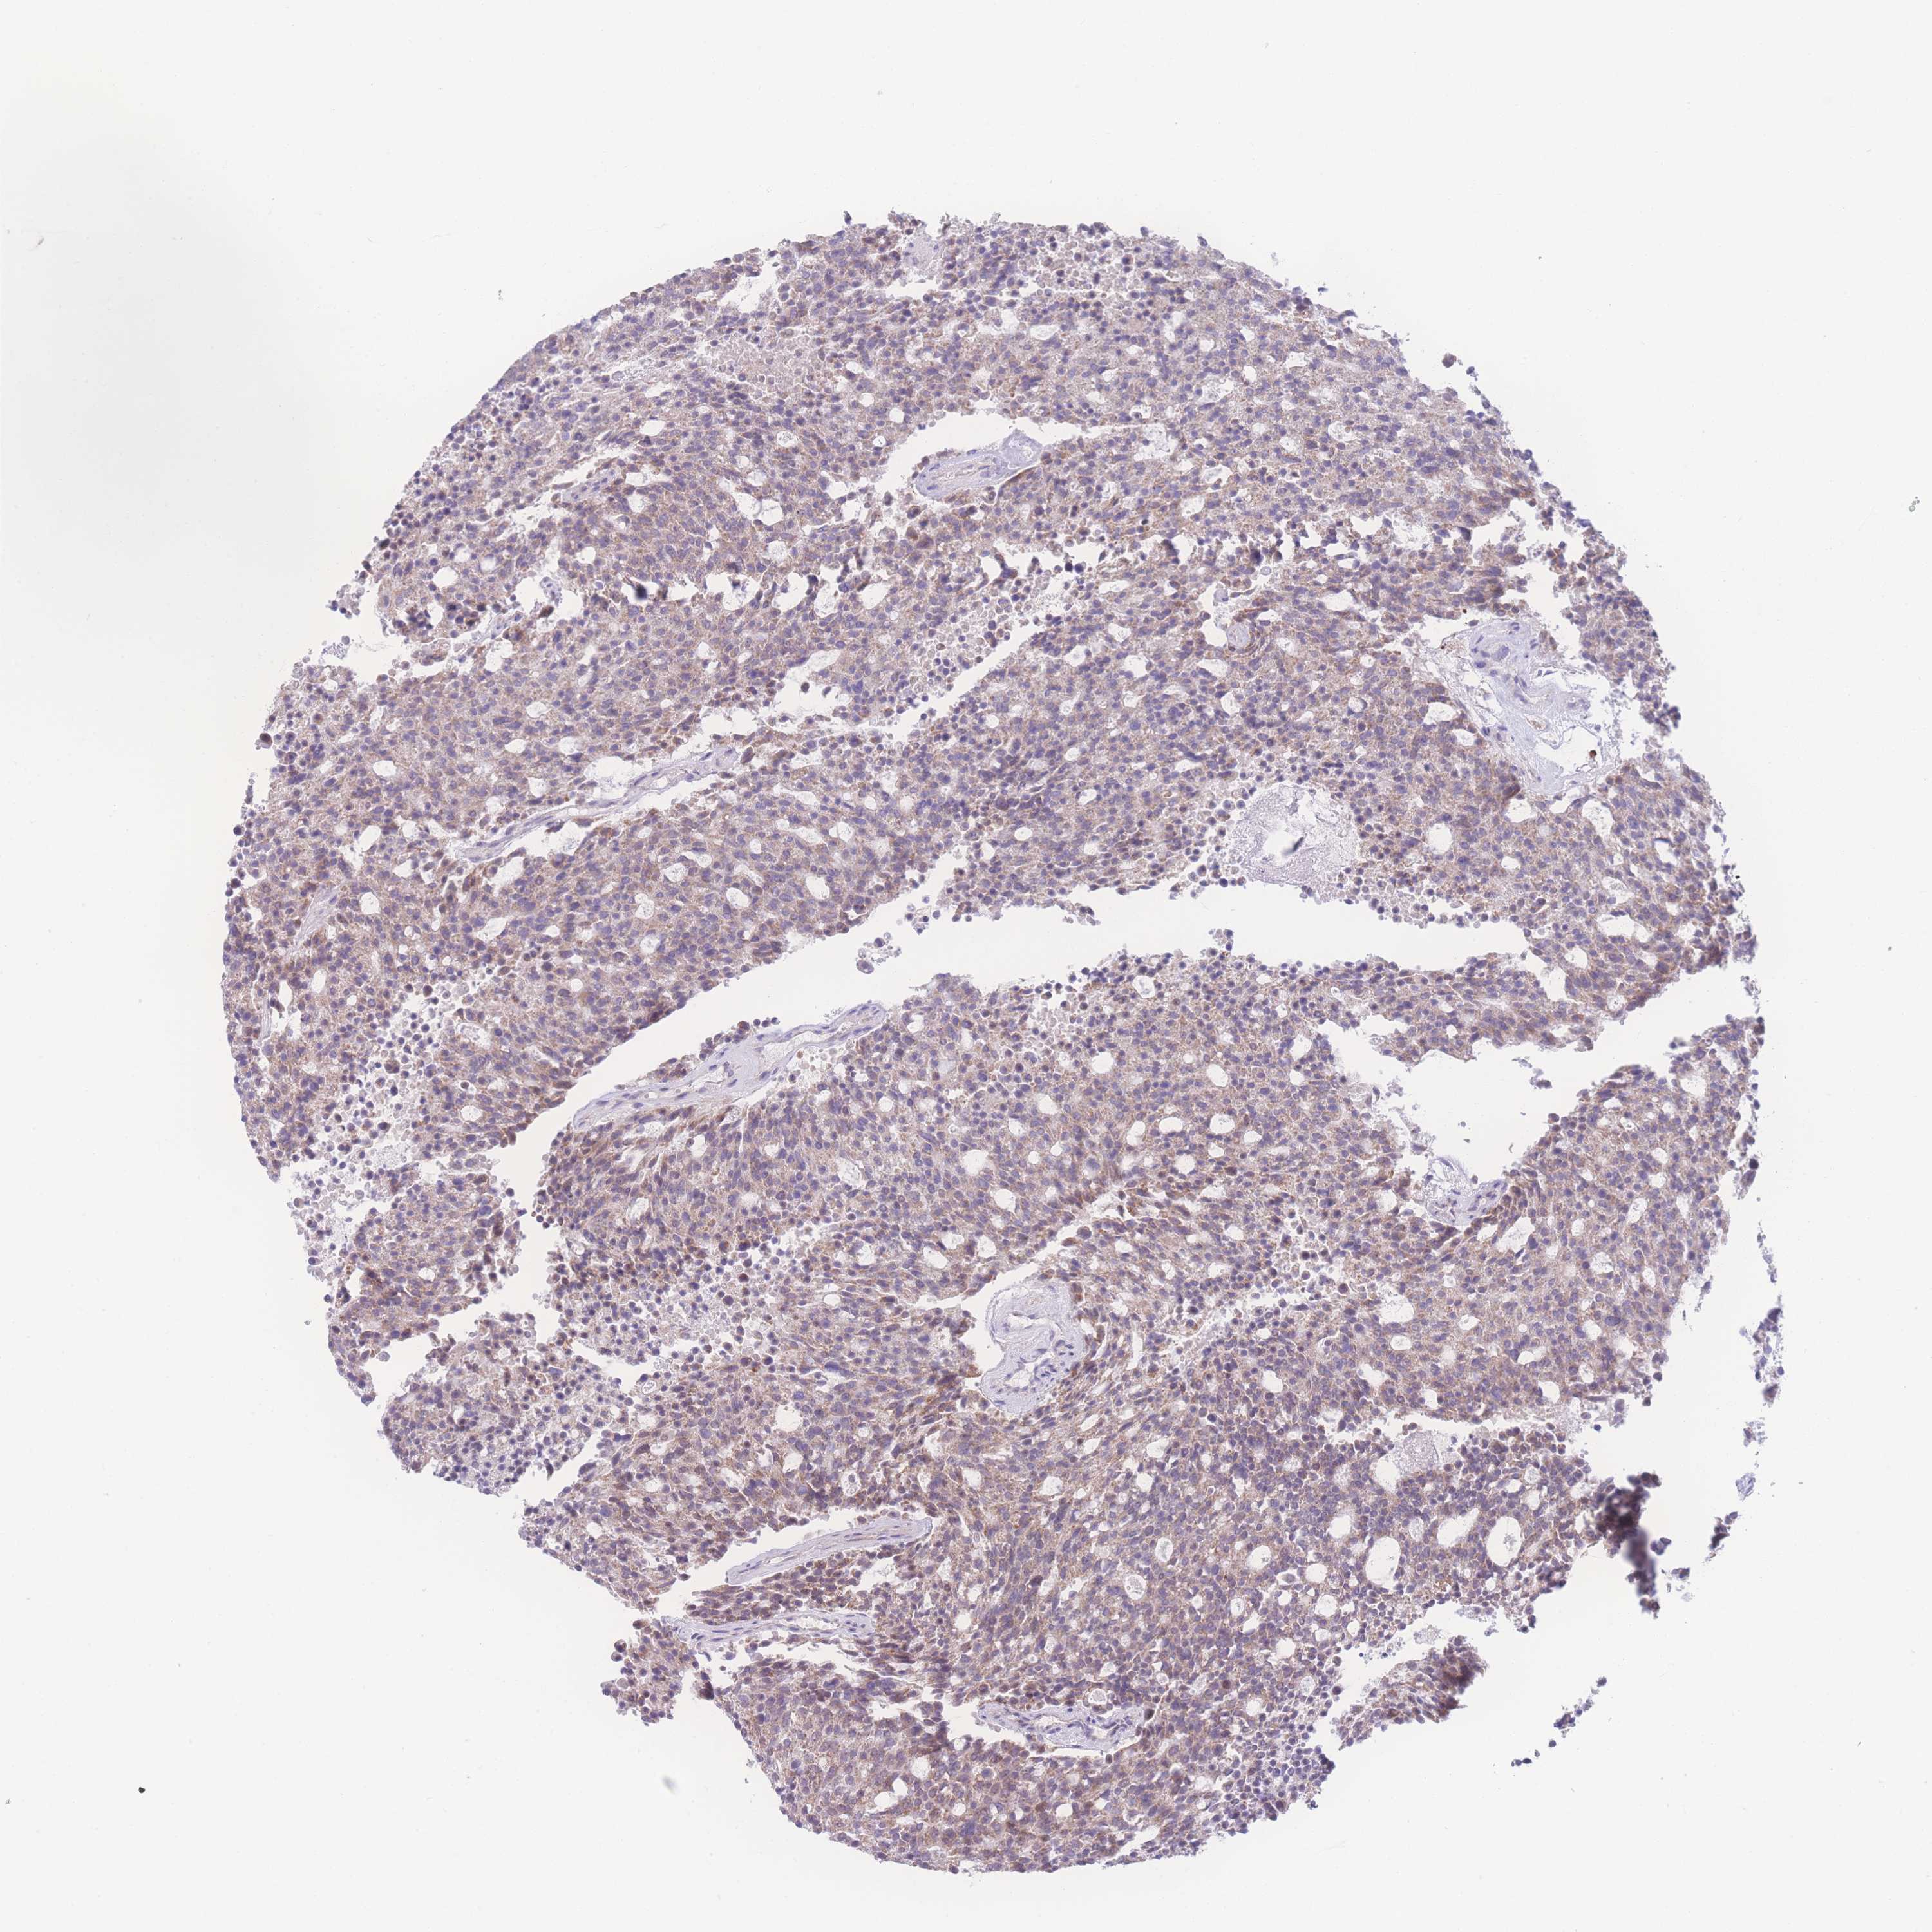

CARCINOID - Protein expressioni

A mouse-over function shows sample information and annotation data. Click on an image to view it in a full screen mode. Samples can be filtered based on level of antibody staining by selecting one or several of the following categories: high, medium, low and not detected. The assay and annotation is described here.

Antibody stainingi

Antibody staining in the annotated cell types in the current human tissue is reported as not detected, low, medium, or high, based on conventional immunohistochemistry profiling in selected tissues. This score is based on the combination of the staining intensity and fraction of stained cells.

Each image is clickable and will lead to virtual microscopy that enables deeper exploration of all samples and also displays staining intensity scores, fraction scores and subcellular localization as well as patient and tissue information for each sample.

Antibody HPA049447

Staining

Medium

Intensity

Moderate

Quantity

75%-25%

Location

Cytoplasmic/membranous

Carcinoid, malignant, NOS